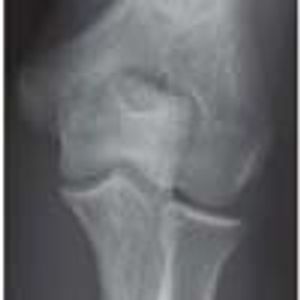

Supracondylar Process

ByAyman Abdul-rauf, MD,Nirav Shastri, MD,Keith Linas, MD,Milton Fowler, MD

A 10-year-old boy injured his left elbow during football practice. He subsequently had pain with normal range of motion of the elbow.